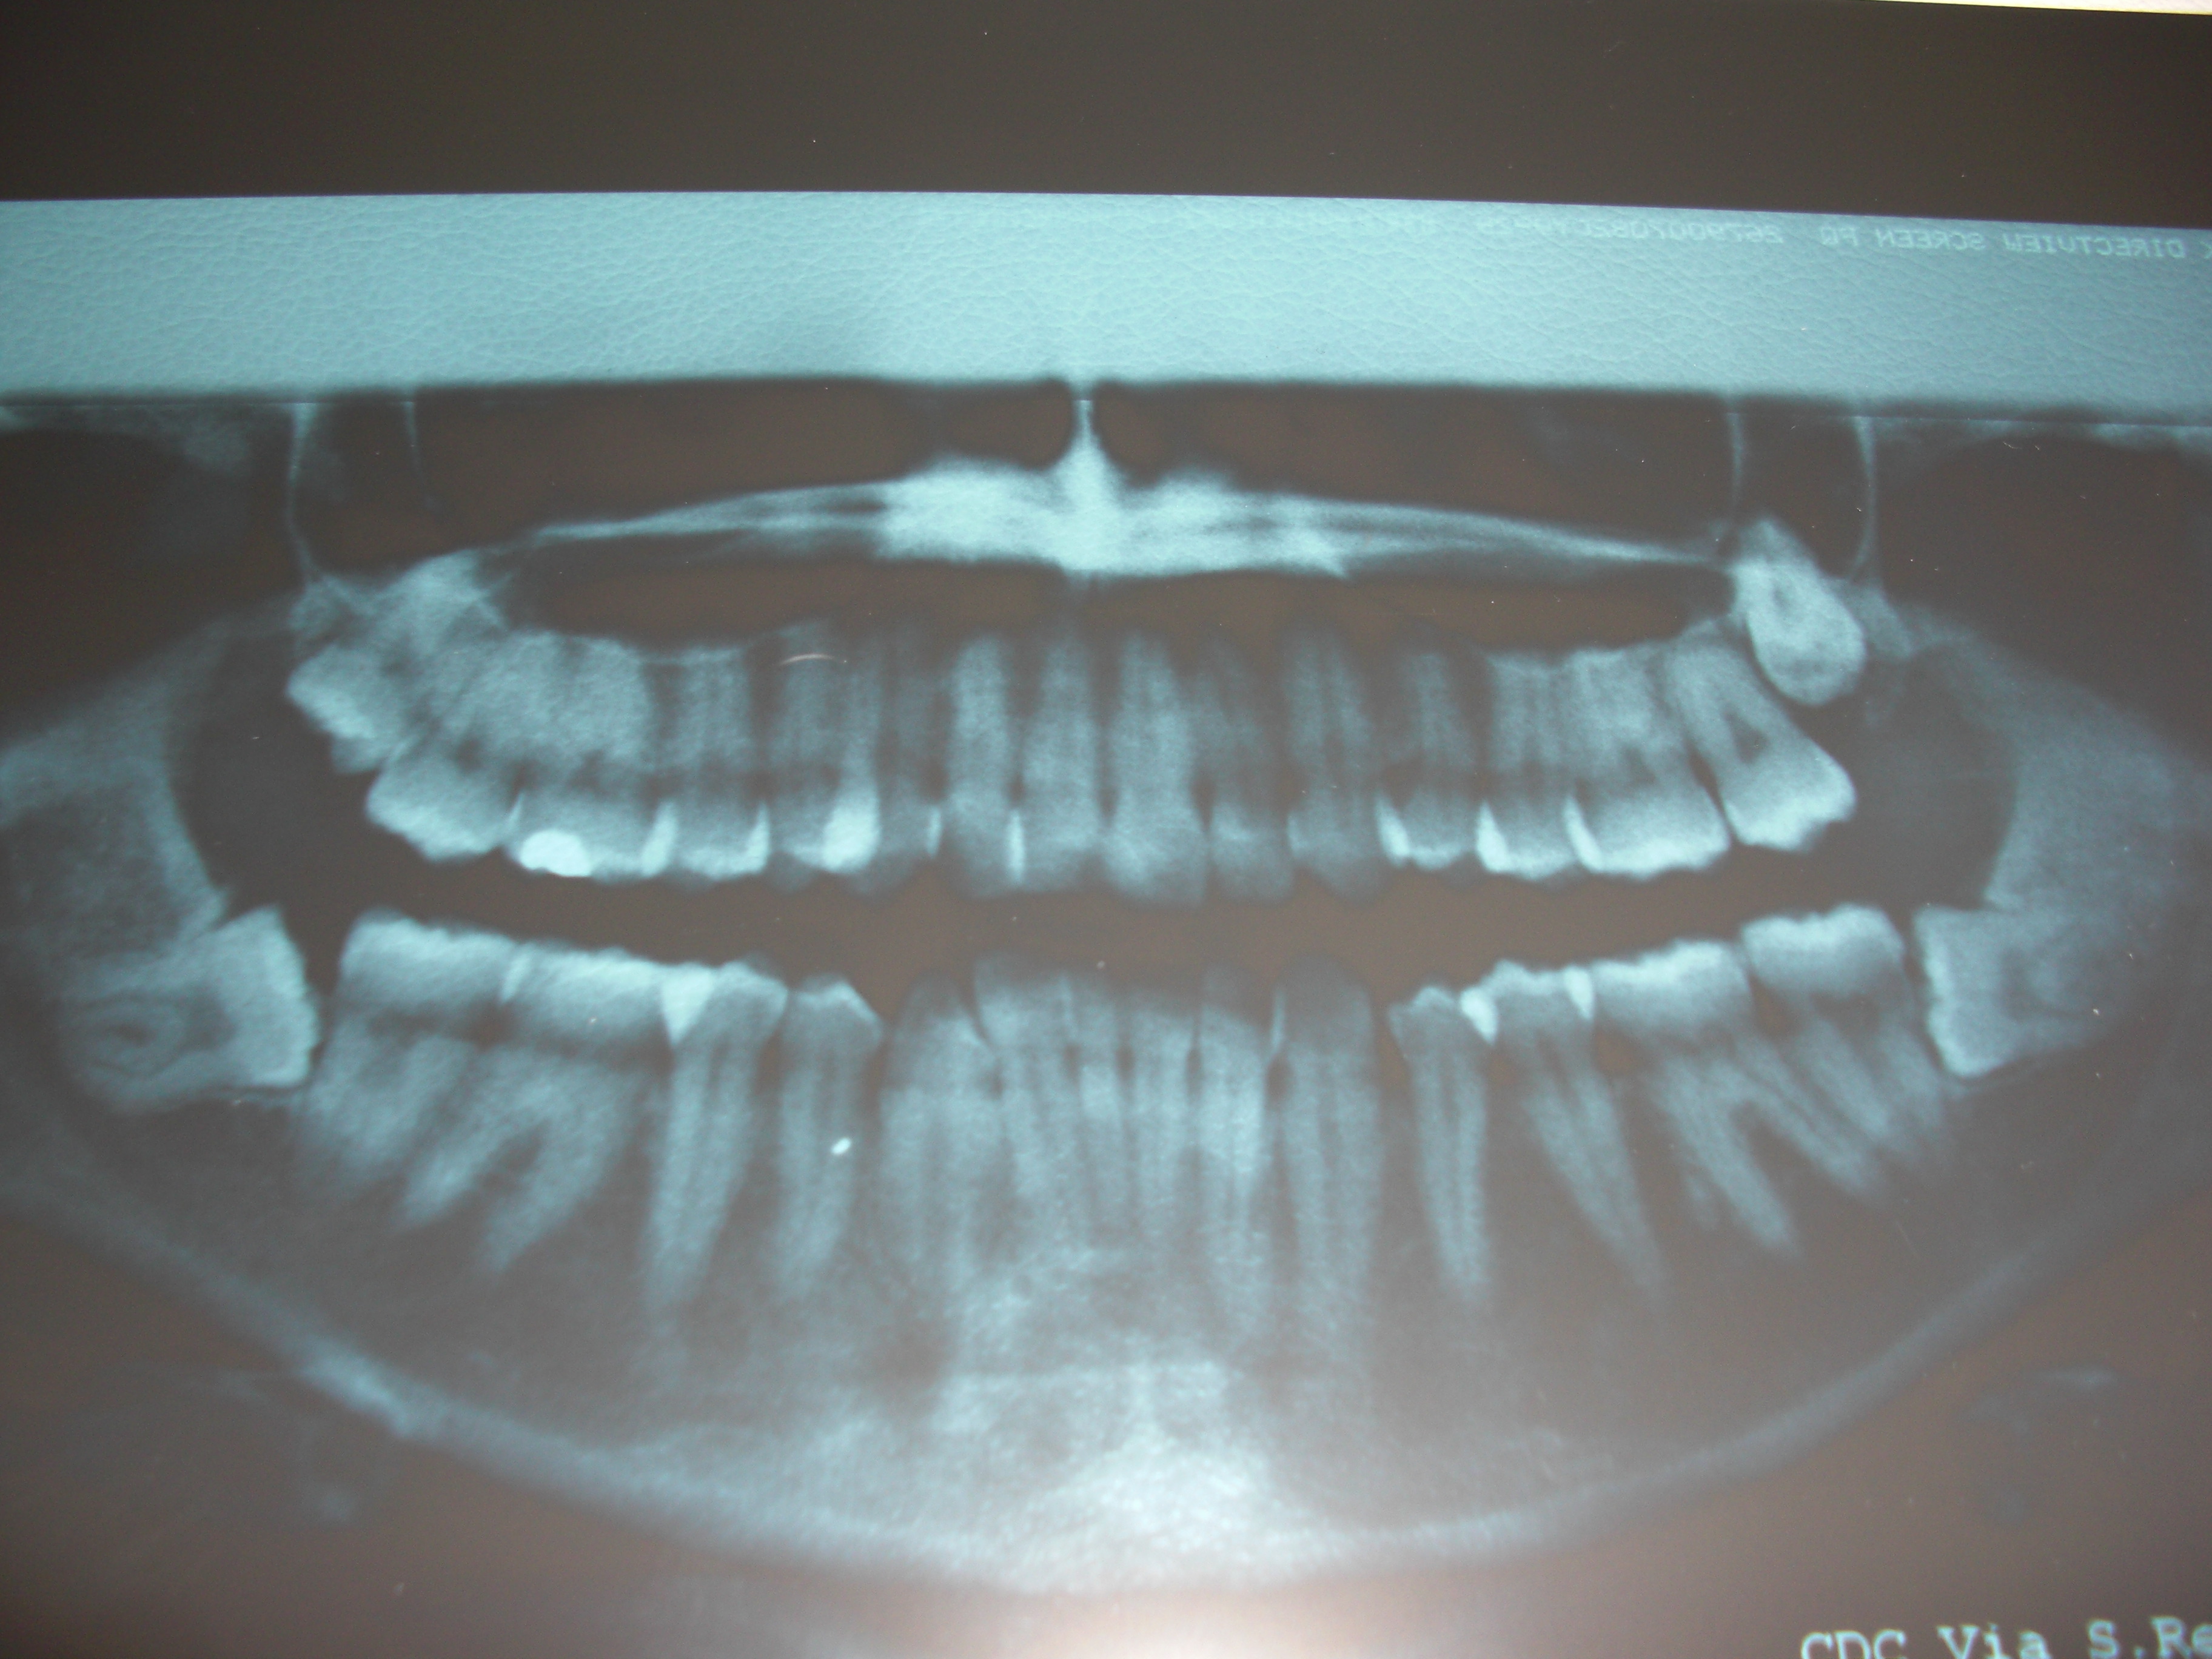

Mi è stato consigliato di togliere tutti e quattro i denti del giudizio

Buon giorno, riporto qui la mia panoramica. Mi è stato consigliato di togliere tutti e quattro i denti del giudizio, per poi mettere un apparecchio, dato che i denti si stanno storcendo per la spinta dei denti del giudizio. L'intervento puo' essere rischioso essendo vicino al nervo mascellare? Cosa consigliate? L'asportazione di tutti e